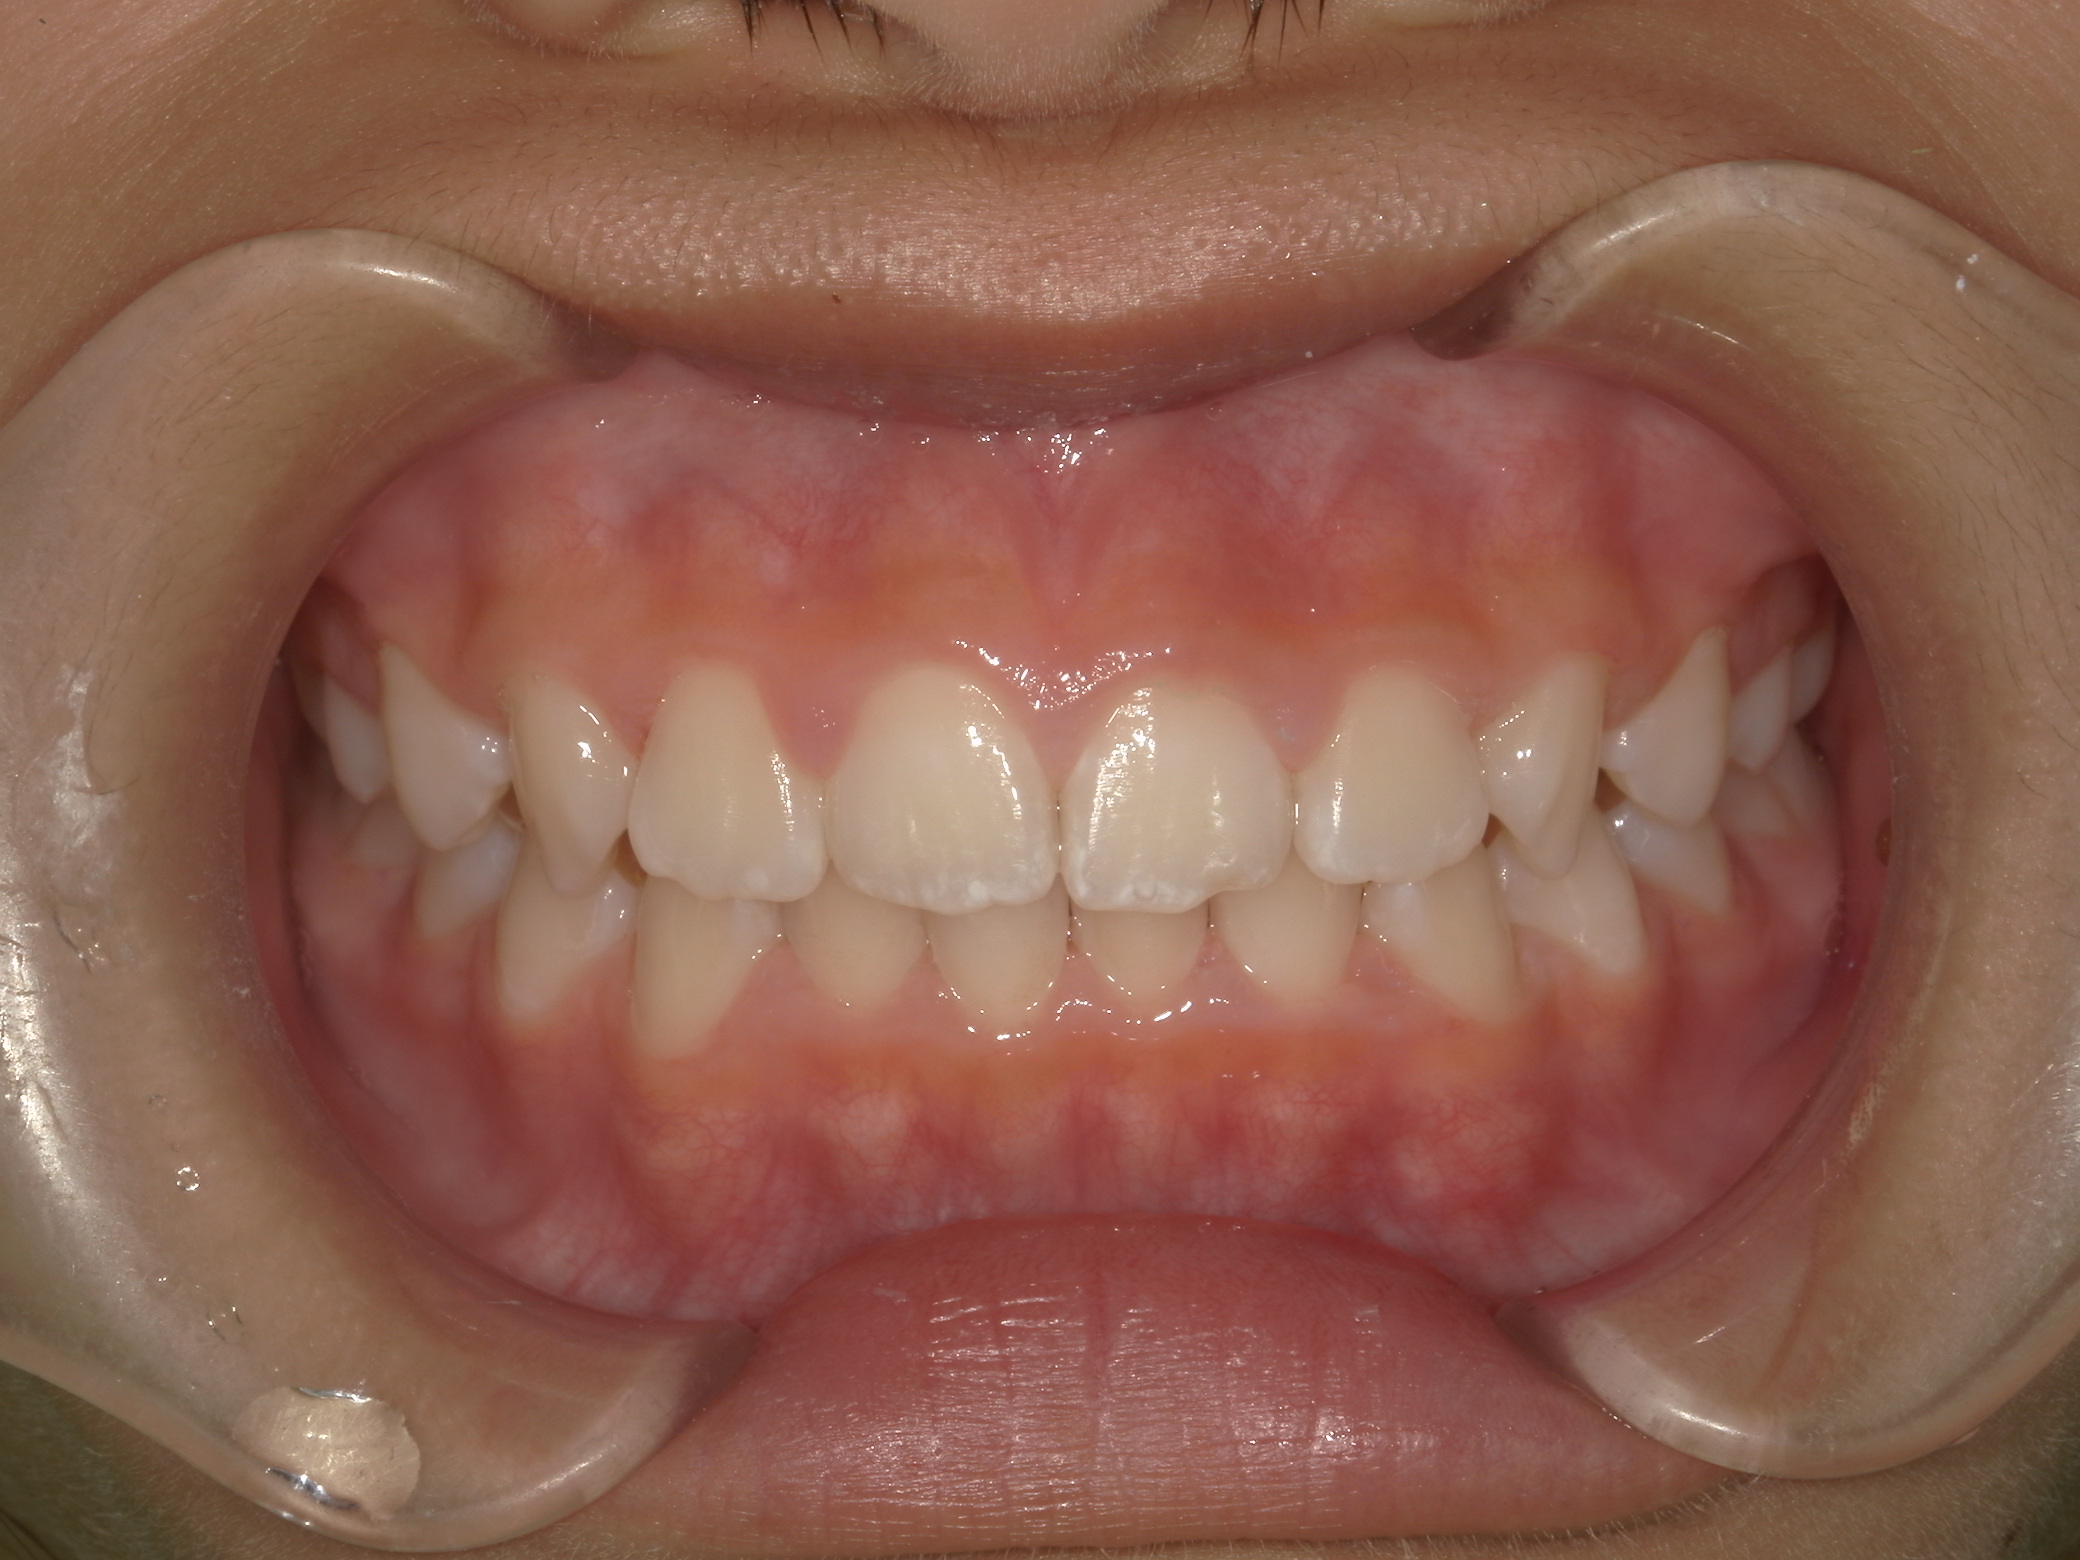

After